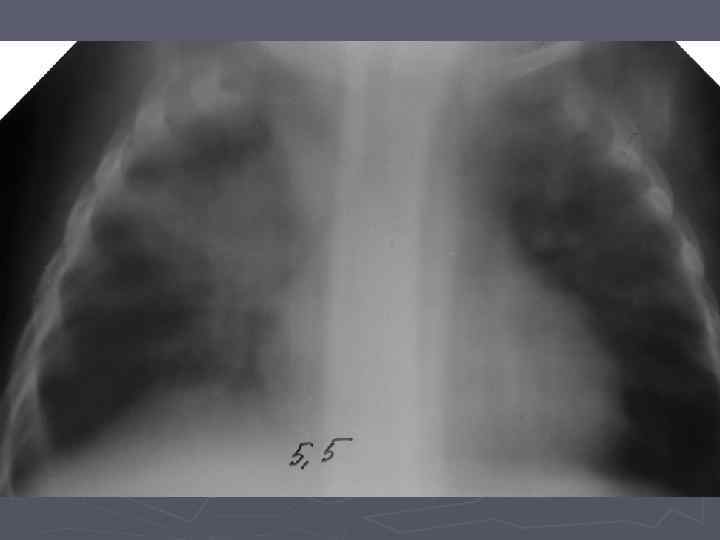

Клинические особенности туберкулеза у взрослых на фоне ВИЧ-инфекции ► ► ► ► ► Внутригрудные аденопатии; Милиарные высыпания; Частое поражение базальных сегментов легких; Относительно редкое поражение каудоапикальных сегментов легких; Распад легочной ткани диагностируется в 2 раза реже; Нередок плевральный выпот; Велика склонность к генерализации туберкулезной инфекции с множественными внелегочными локализациями. Присоеднинение туберкулезного менингита; МБТ в мокроте выявляются одинаково часто у ВИЧ негативных и позитивных лиц, по крови МБТ методом посева выделяются у 70% пациентов; При отсутствии признаков локального туберкулеза и неясной лихорадке – посев костного мозга часто дает МБТ+.

Клинико-эпидемиологические особенности туберкулезной инфекции у ВИЧинфицированных и больных СПИДом детей ► Вертикальный путь заражения ВИЧ; ► Ранний возраст; ► Семейные контакты с болеющими туберкулезом в активных фазах; ► Отсутствие вакцинации БЦЖ; ► Выраженный локальный процесс, протекающий с: § бронхолегочными поражениями; § Распадом легочной ткани; § Обсеменением легочной ткани.

Неблагоприятное сочетание ряда обстоятельств: § Ранний возраст; § Тяжелые семейные контакты; § Отсутствие вакцинации - и у свободных от ВИЧ-инфекции детей всегда приводят к развитию локального туберкулеза, протекающего, как правило, ОСЛОЖНЕННО с бронхолегочными поражениями, распадом легочной ткани, диссеминациями.